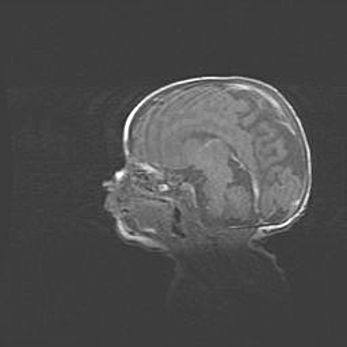

Наружная гидроцефалия с возможной атрофией височных областей.

Возраст: 28 дней

Вес: 3670 г

Пол: мужской

Окружность головы: 38 см

Срок гестации: 40 недель

Гидроцефалия головного мозга у новорожденных – это заболевание, которое характеризуется скоплением избыточного количества спинномозговой жидкости в желудочковой системе головного мозга в результате затруднения её перемещения от места выработки к месту поглощения в кровеносную систему или вследствие нарушения абсорбции. При открытой наружной форме гидроцефалии у новорожденных расширяются и переполняются субарахноидные пространства.

При нормотензивных  формах,  которые,  как  правило,  являются  следствием  перенесенных ишемических  повреждений  паренхимы  мозга,  возможно  сочетание микроцефалии  с нормотензивной гидроцефалией. В основе данных изменений лежит атрофия больших полушарий с преимущественной  локализацией  в  лобно-височных  областях.